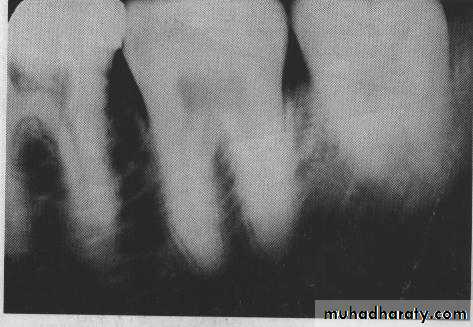

CONTRAST: It is the difference in densities between light and dark regions on a radiograph.

Densities on radiograph are not simply black and white but encompass multiple shade of gray called scale of contrast.

High-contrast image(short scale contrast)would be black and white with few gray shade.

Low-contrast images(long-scale contrast)usually contain a wide rang of shades of gray.